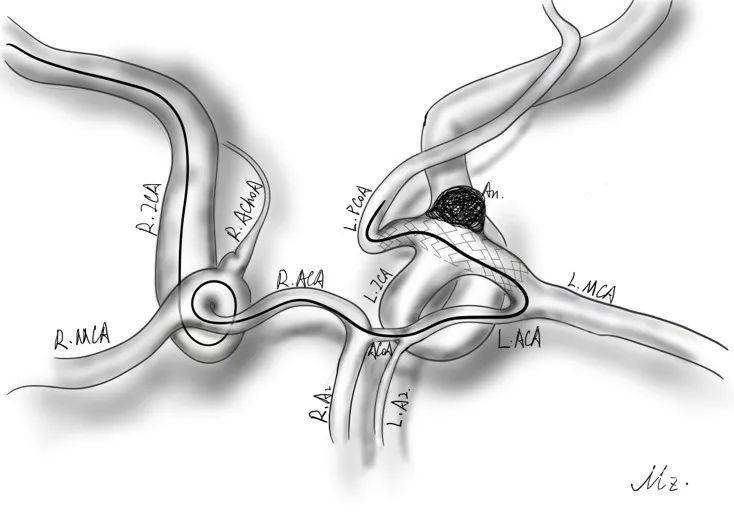

1)动脉瘤多发子瘤累及动脉瘤颈及瘤体,弹簧圈裸栓存在脱落风险,且难以使近瘤颈处子瘤致密栓塞。因此,需支架辅助动脉瘤栓塞。

2)但动脉瘤累及颈内动脉交通段与后交通动脉起始部。支架由左侧颈内动脉至后交通动脉放置不能完全封闭瘤颈,致密填塞弹簧圈可能导致弹簧圈溢出而影响颈内动脉末端血流。

右侧远端通路导管(心玮6F 115cm)置于左侧颈内动脉破裂孔段提供支撑,必要时跟进至眼动脉段。使用Synchro-14 200cm微导丝携Echelon-10(45° Tip-shaped)在双侧路图引导下超选通过前交通动脉。微导丝超选至左侧颈内动脉眼动脉段以带动微导管通过迂曲的前交通复合体,进入颈内动脉末段,为进一步超选后交通动脉做准备。

微导丝超选通过后交通动脉进入大脑后动脉P2段,为跟进微导管提供足够支撑。跟进微导管置于左侧大脑后动脉P2段,为通过支架时的导管后撤提供缓冲。

左侧(患侧)同样置入远端通路导管(心玮6F 115cm)于岩段。经双侧减影确认支架导管就位。经左侧远端通路导管送入预塑形的Echelon-10(45°Tip-Shaped)微导管在Synchro-10导丝辅助下超选入动脉瘤腔,分别置于瘤顶和瘤颈。

经位于瘤顶的微导管送入Target 360 SOFT 3mm*6cm弹簧圈尝试成篮,但弹簧圈逸出,遂释放Atlas 3mm*21mm支架。由于血管迂曲,支架释放位置后撤,覆盖后交通动脉起始部至左侧大脑前动脉A1起始部,瘤颈覆盖满意。